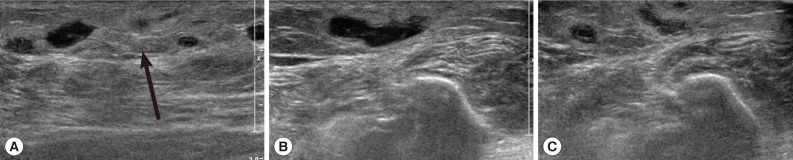

During the surgery, a longitudinal incision was made on the lateral aspect of the right lower leg. A soft, movable, and poorly marginated mass with a diameter of 2 cm was observed. The same as the previous operation, a white-shiny, synovium-like piece of body popped out through the incision, and determined as a sparganum. The removed worm was 15 cm in length, slightly shorter than that of the previously removed one (18 cm in length), and the scolex was easily seen (

Fig. 2). After removing the sparganum, neuroraphy was performed because a ruptured sural nerve was observed. The pathological examination revealed chronic granulomatous inflammation with a degenerating parasite caused by a parasitic (possibly sparganum) infection. The patient's symptoms were improved thereafter and considered not reappeared again for more than 2 years after the second operation.

Fig. 2A photograph of the removed sparganum with its scolex (box).